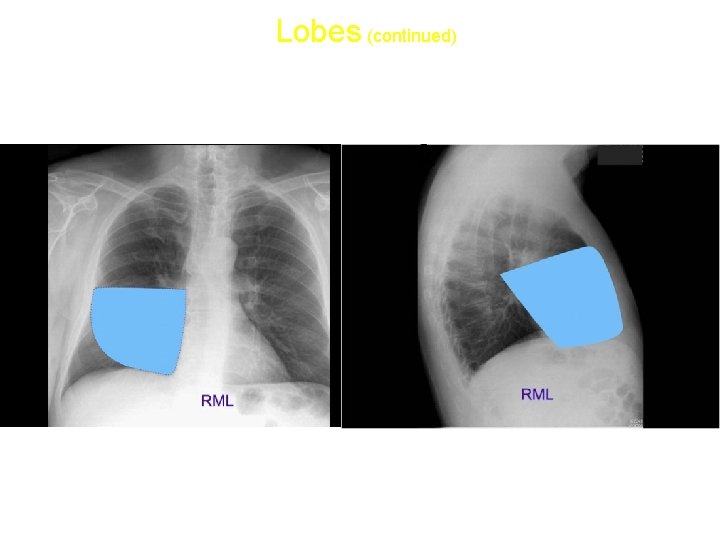

Lobes (continued) • Right middle lobe: